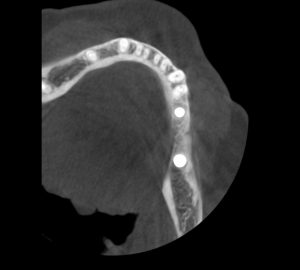

Теперь возьмём клинический случай (нижняя челюсть, отсутствия 35, 36, 37 зубов, атрофия альвеолярного гребня по ширине):

и рассмотрим его через парадигму методологического редукционизма. Или, если хотите, сквозь Бритву Оккама.

Мы имеем относительно небольшой дефект, не позволяющий, однако, установить имплантаты правильного размера в правильное положение. И два варианта остеопластической операции, НКР и АТККФ.